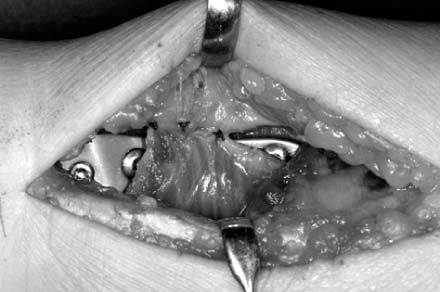

jkfs-21-325-g009.jpg

Fig. 10

A dotted line indicates transverse ridge, and the fracture site is exposed after elevation of pronator quadratus.

Fig. 10 A dotted line indicates transverse ridge, and the fracture site is exposed after elevation of pronator quadratus.